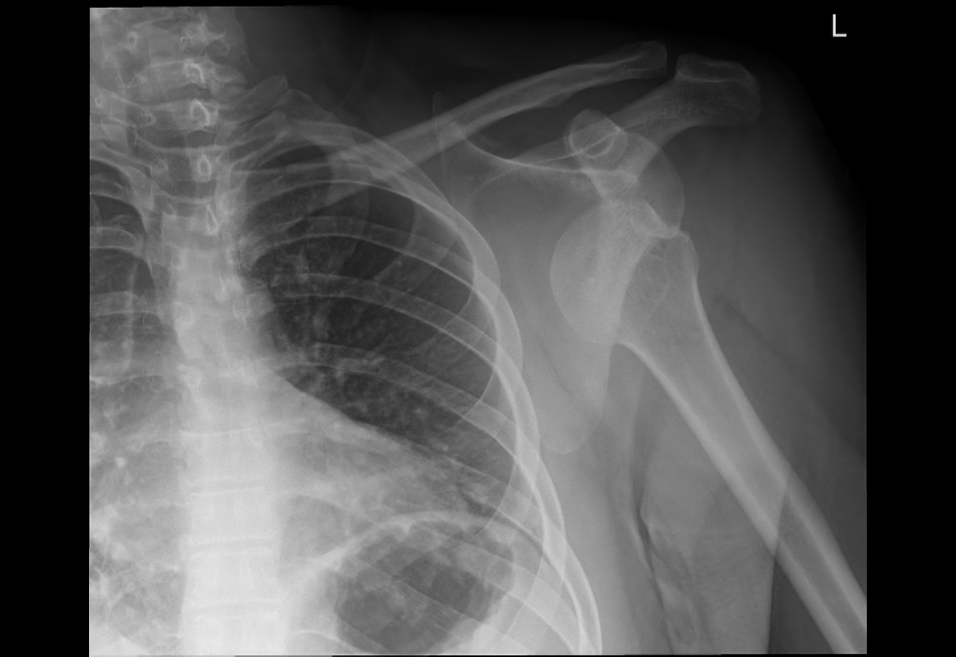

They X-rayed me to see the complete situation and check for fractures before they poped the shoulder back in.

as you can see its not where it should be. I could feel it pressing against my ribs. There is a slight fracture on the head of the bone.